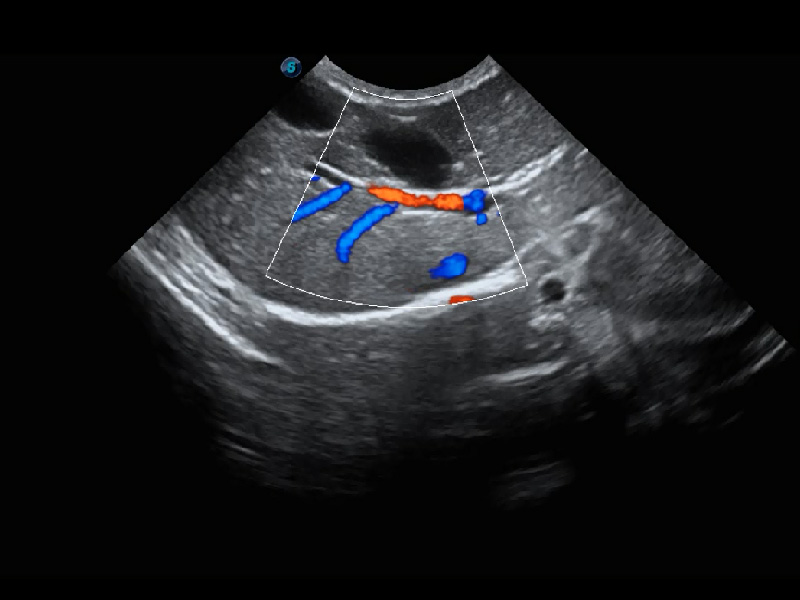

4T血流成像 微察秋毫

融合不同血流成像技术的优势,即可以提升血流成束性,同时可提高血流的视觉敏感性。

优异的基础图像

(犬)肾脏血流